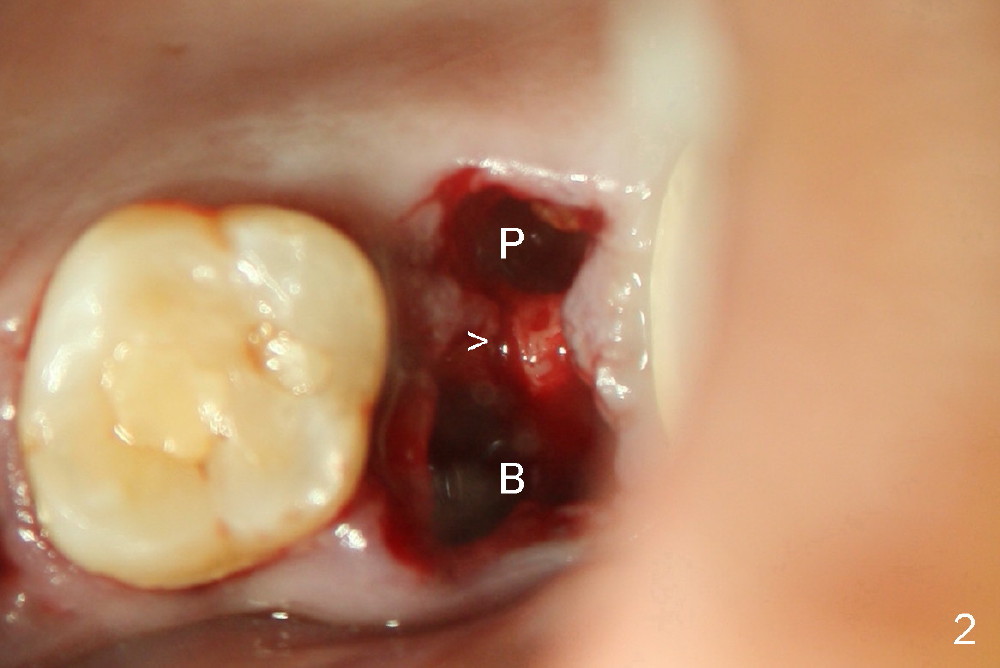

A 43-year-old lady has multiple nonsalvageable teeth. The first surgery involves two immediate implants in the upper left sextant (Fig.1: #13 and 15). The tooth #15 has 3 residual roots (MB, DB, P). There is no septum left between the first two roots when the tooth is extracted. A septum exists between the palatal (P) and buccal (B) sockets (Fig.2). Bone expansion technique is utilized to create an osteotomy in the septum. However, the smallest rounded tapered osteotome cannot be driven into the narrow septum; it slides (Fig.5). To get an initial engagement, a slot is created by high-speed surgical handpiece and fissure bur on the top of the septum. A series of blade-like osteotomes are inserted into the septum for sectioning (Fig.2 >). The smallest rounded osteotome is now easy to be inserted into the middle of the septum (Fig.3 circle, Fig.6 O). The septum is expanded by larger osteotomes (Fig.4 white circle; Fig.7 O) and tap (Fig.9 T). The septum continues being expanded when a 6x14 mm implant is placed (Fig.8,10 I). The insertion torque is more than 60 Ncm. No bone graft is placed. The palatal gap is closed by a palatal flap.